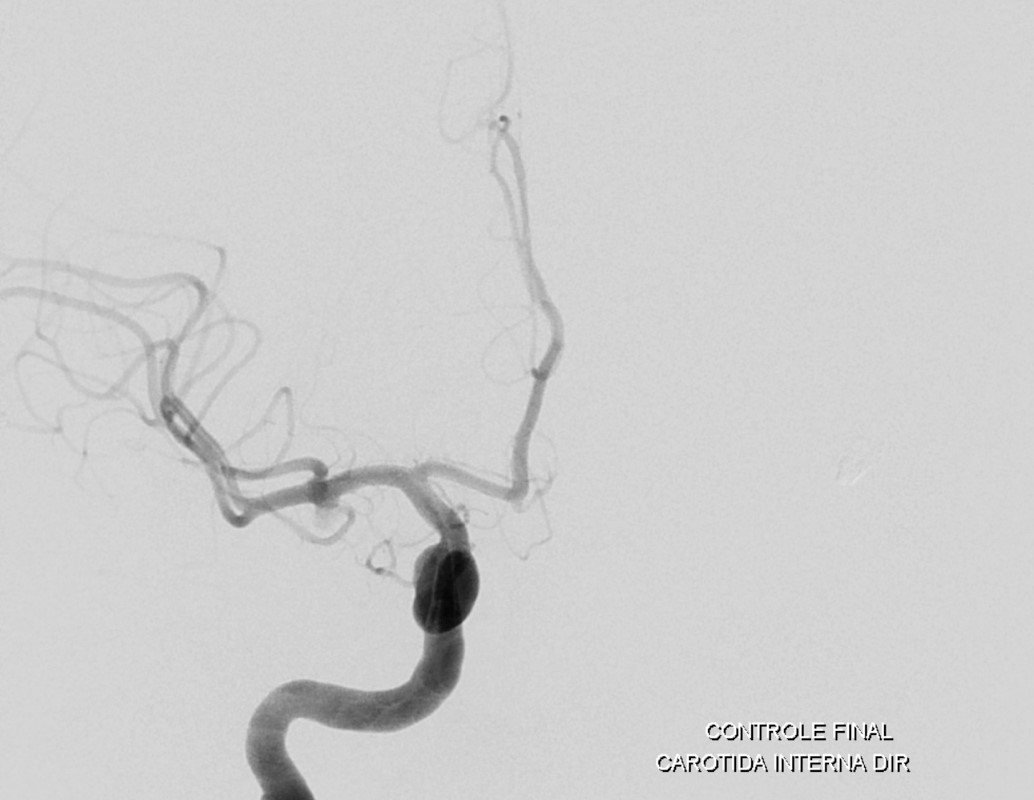

Aneurisma incidental relacionado a artéria cerebral média diagnosticado após investigação de cefaleia. Realizado tentativa de embolização com micromolas sem sucesso, sendo optado pelo tratamendo endovascular com stent redirecionador de fluxo Fred Jr 03 x 14 x 19 mm.